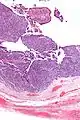

| Micrograph of transitional cell carcinoma of the ovary. H&E stain. |

Transitional cell carcinoma of the ovary (TCC of the ovary) is a rare type of ovarian cancer that has an appearance similar to urothelial carcinoma (also known as transitional cell carcinoma).[1]

TCC of the ovary is diagnosed by examination of the tissue by a pathologist. It has a characteristic appearance under the microscope and distinctive pattern of immunostaining.[2]

Low mag.